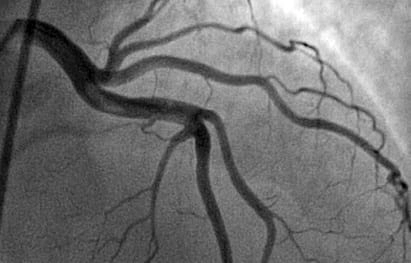

Коронарография — наиболее информативный метод исследования состояния коронарных артерий. Малоинвазивная и безопасная процедура, «золотой стандарт» для определения степени атеросклеротического поражения сосудов сердца и диагностики ишемической болезни сердца. С помощью коронарографии врач может точно определить, на каком участке и насколько сужены артерии и какие существуют риски для пациента. В АО «Медицина» исследование проводят опытные сердечно-сосудистые хирурги в рентгеноперационной, оборудованной ангиографом последнего поколения GE Healthcare Innova IGS 530. Процедура безопасна, безболезненна, не является обширным вмешательством, поэтому на восстановление не потребуется много времени.

Коронарография необходима для точной диагностики ишемической болезни сердца (ИБС), которая на сегодня является одним из самых опасных жизнеугрожающих заболеваний, согласно Всемирной организации здравоохранения. Среди наиболее опасных патологий медики выделяют стеноз ствола левой коронарной артерии. Причиной тому является риск фатального исхода и высокая распространенность патологий. Стеноз ствола левой коронарной артерии сегодня фиксируют у 5-7% больных, страдающих от ИБС. Это поражение входит в группу высокого риска, так как именно через этот отдел проходит около 75-100% крови, питающей миокард сердца. Отсутствие точной диагностики и своевременного лечения грозит пациентам со стенозом ствола левой коронарной артерии риском развития нарушения деятельности левого желудочка и даже смертью.

Специалисты АО «Медицина» с абсолютной точностью определят степень и характер сужения просвета коронарной артерии. Для каждого клинического случая вам определят тактику лечения.

Лечение сердечно-сосудистых заболеваний невозможно сегодня представить без точных и современных методов диагностики. Коронарография является «золотым стандартом» для выявлении атеросклеротических бляшек. В АО «Медицина» это исследование проводится на передовом медицинском оборудовании – последнего поколения. Многолетний опыт врачей нашей клиники и самое современное оборудование помогут вам в кратчайшие сроки вернуться в привычному образу жизни и избежать серьезных последствий

Сама процедура длится недолго — до 40 минут. В области запястья делается прокол артерии и устанавливается специальное устройство с клапаном, которое не даст открыться кровотечению. Далее в артерию вводится интродьюсер (полая трубка – проводник). После этого с помощью тонкого катетера в исследуемые артерии вводится контрастное вещество, которое позволяет сделать рентгеновские снимки в реальном времени. Так получается ангиограмма, позволяющая врачу оценить степень поражения сосудов. После процедуры на место прокола накладывается тугая повязка.